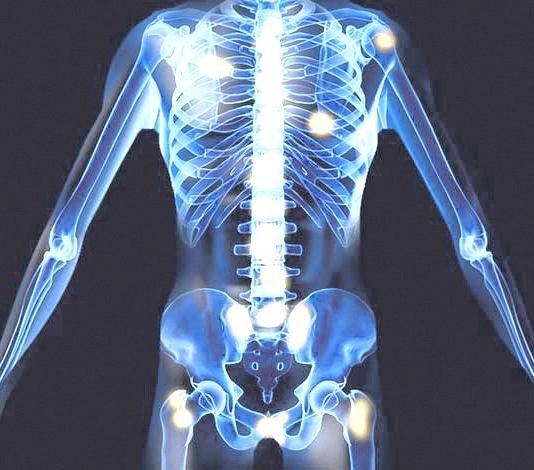

- 설명: 전립선암은 다른 암과 달리 **뼈(골격)**로 전이되는 경향이 매우 강합니다. 초기에는 증상이 없을 수 있지만, 암이 국소적으로 진행되거나 뼈로 미세하게 전이되기 시작하면 허리 아래쪽(요추), 골반, 엉덩이 부위에 간헐적이거나 지속적인 통증이 나타날 수 있습니다. 이러한 통증은 전립선암의 중요한 진행 신호일 수 있습니다.